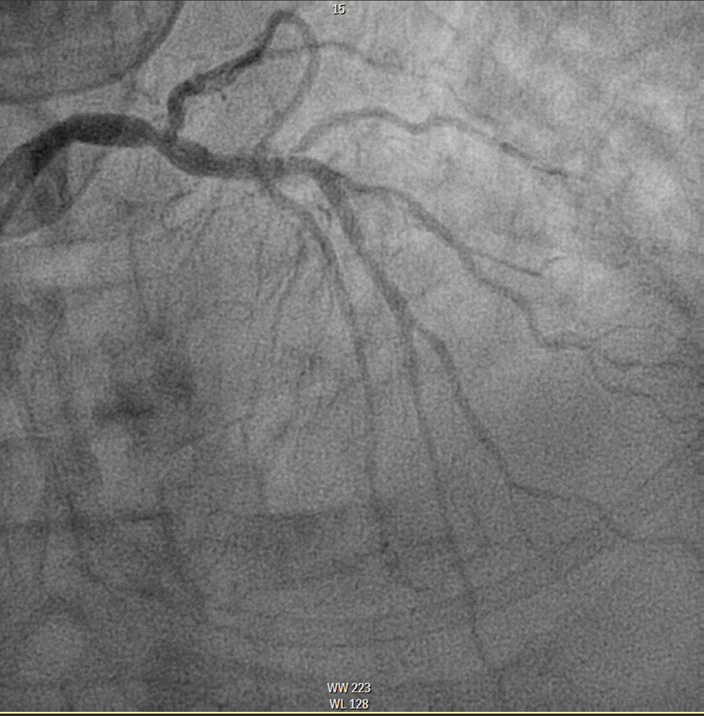

*Coronary angiography: On arrival at the hemodynamics unit, a diagnostic study was performed through the right radial artery in which TIMI 3 flow was observed throughout the coronary tree with no obstructive lesions in the coronary arteries. Good late results of Everolimus-eluting stents previously implanted in the middle LAD, distal LAD and ostial PD. Good result of PTCA on OCT of ostial CX with distal bed of moderate caliber. Moderate lesion at distal CT level (assessed by IVUS). (Figures 3 and 4)

Figure 3 CD without significant lesions.

Figure 4 Moderate injury at the distal CT level.